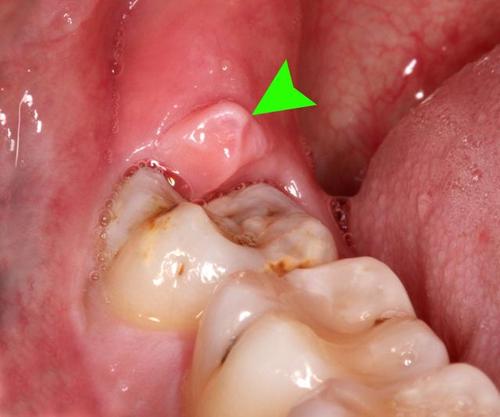

智齿包肉里怎么办图片

智齿包肉里怎么办图片,智齿包在肉里面图片

智齿牙后面长了一小块肉,这是怎么回事啊?

大夫说智齿位置长的正着呢,不用拔了,等消炎了把牙齿上盖的肉割了应该

智齿包在肉里面图片

肉包智齿图片

智齿半包在肉里面图片

智齿后面的肉肿了图片

牙齿被肉包住了图片

尽头牙长肉包裹图片

智齿长出一半被肉包着

智齿露一半包一半图